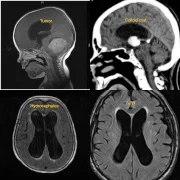

At our advanced Neurosurgery Center in Thane, we specialize in brain tumor surgery with a focus on both complete tumor removal and the preservation of neurological functions. Using modern techniques such as microsurgery, endoscopic brain surgery, and neuronavigation systems, our neurosurgeons ensure safe and precise treatment. Whether it is a glioma, meningioma, pituitary tumor, or metastatic brain tumor, we provide personalized surgical care for the best outcomes. Patients benefit from shorter hospital stays, faster recovery, and improved quality of life after surgery.

We provide advanced treatment for hydrocephalus with modern shunt surgery in Thane. Hydrocephalus occurs due to excess cerebrospinal fluid buildup in the brain, leading to pressure-related complications. Our neurosurgeons perform Ventriculo-Peritoneal (VP) shunt procedures and endoscopic third ventriculostomy (ETV) to safely divert or regulate the fluid. We focus on safe surgery, minimal risks, and long-term results for both pediatric and adult hydrocephalus patients.

Our specialized pediatric neurosurgery services in Thane provide advanced care for children with congenital brain malformations, hydrocephalus, spinal cord defects, spina bifida, craniosynostosis, and pediatric tumors. With child-friendly infrastructure, advanced anesthesia support, and experienced pediatric neurosurgeons, we ensure safe and compassionate care tailored to the unique needs of children.